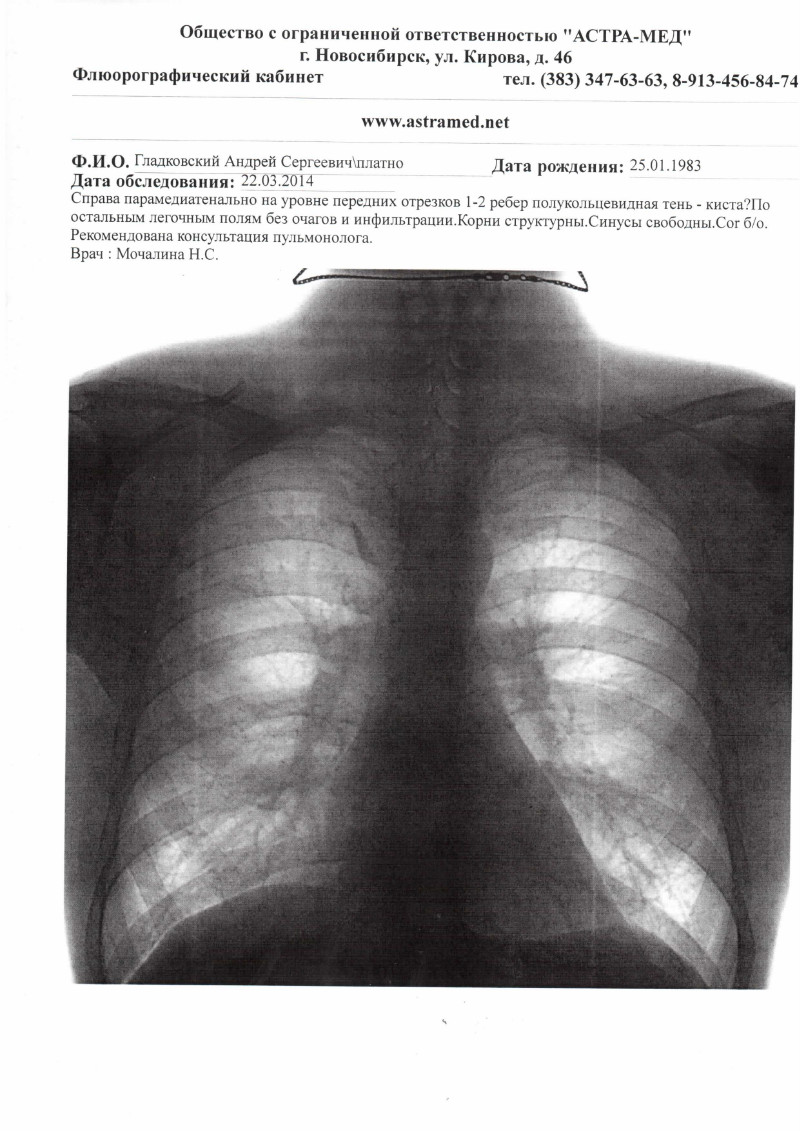

Фотографии рентгеновских снимков без необходимости направления от врача